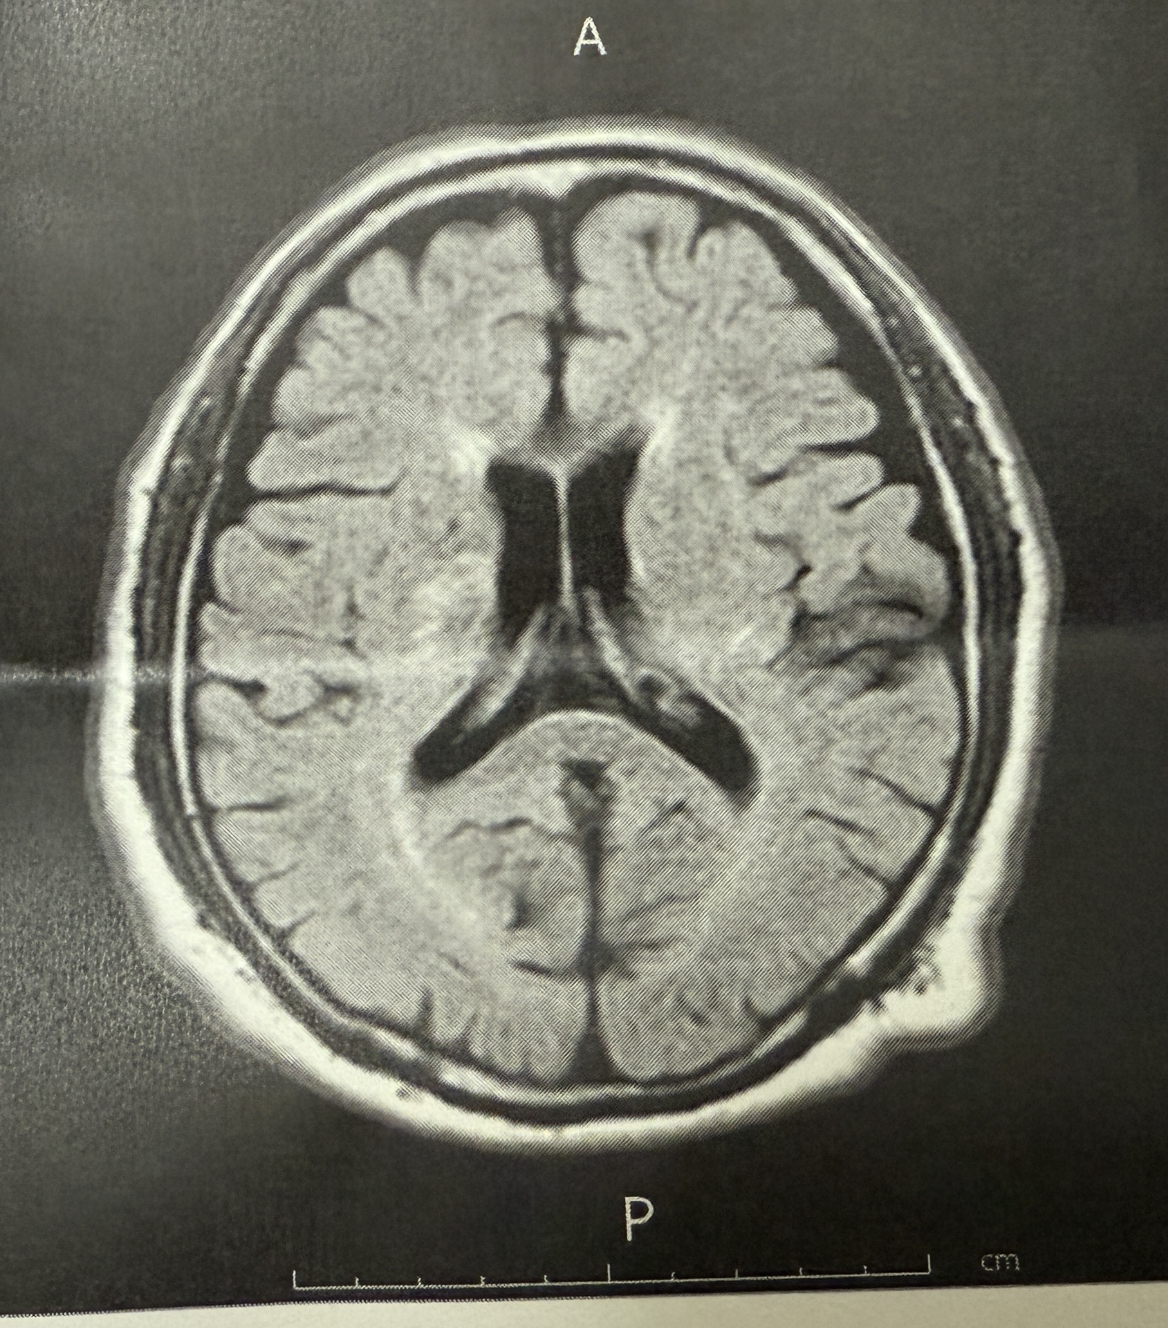

それでも、循環器科の先生が連絡を取ってくれたところ、MRIが空いていたそうで、14時半過ぎにMRI検査を受けられたそうです。

夫は「アテローム血栓症の脳梗塞」と診断され、2週間以内に再発する可能性があるそうです。